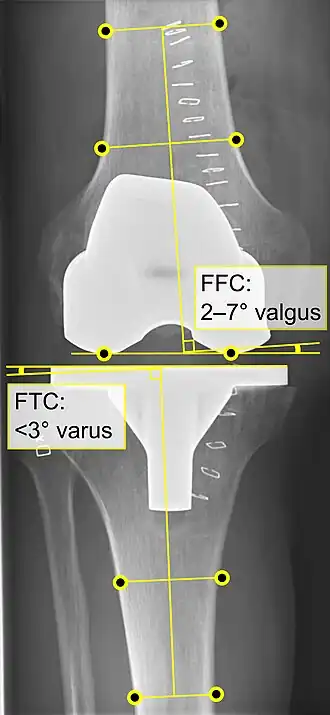

El reemplazo de rodilla se evalúa de forma rutinaria mediante rayos X, incluidas las siguientes medidas:

- CFF: ángulo del componente femoral frontal. Por lo general, se considera óptimo cuando se encuentra entre 2 y 7° en valgo.[55]

- CTF: ángulo del componente tibial frontal, que se considera óptimo cuando se encuentra en ángulo recto. En general, se ha encontrado que una posición en varo de más de 3 ° aumenta la tasa de falla de la prótesis.[55] -